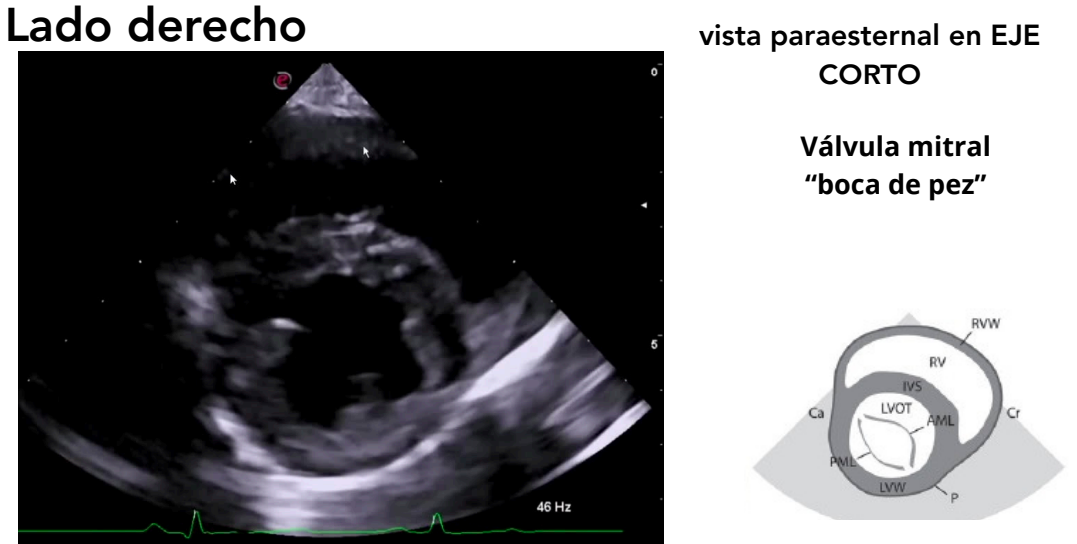

Vista paraesternal en eje corto

- Niveles observables:

- Músculos papilares ("champiñón")

- Válvula mitral ("boca de pez")

- Base cardíaca

- Tracto de salida del ventrículo derecho

El ratio atrio izquierdo/Aorta se mide con la vista paraesternal en eje corto de base cardiaca